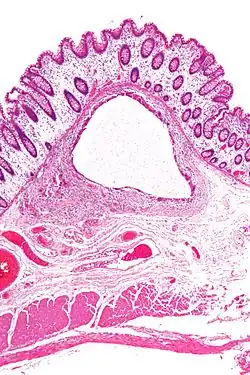

- Pneumatosis intestinalis, air or gas cysts in the bowel wall

- Gastric pneumatosis (or gastric emphysema) is air or gas cysts in the stomach wall[6]